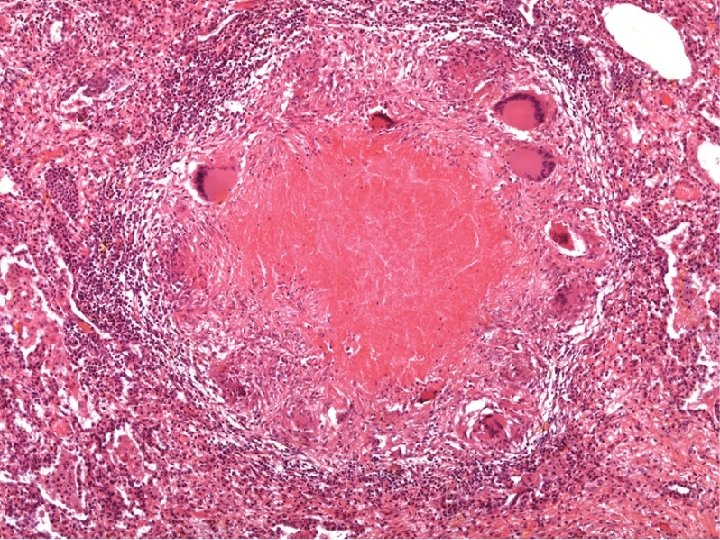

2. Granulomatous inflammation � Granulomatous inflammation is a distinctive pattern of chronic inflammation characterized by aggregates of activated macrophages with scattered lymphocytes. These macrophages will be activated and modified to be similar to epithelial cells so called: Epithelioid cells. q Many epithelioid cell united together forming: Giant cell. q A dense membrane of connective tissue encapsulates the lesion and isolates it. q

Diagram of typical TB granuloma Multinucleated GC Epithelioid cells Caseation necrosis Lymphocytes Firoblasts

Giant cells The epithelioid cells coalesce, forming a large, multinucleated giant cell that attempts to surround the foreign Agent. .